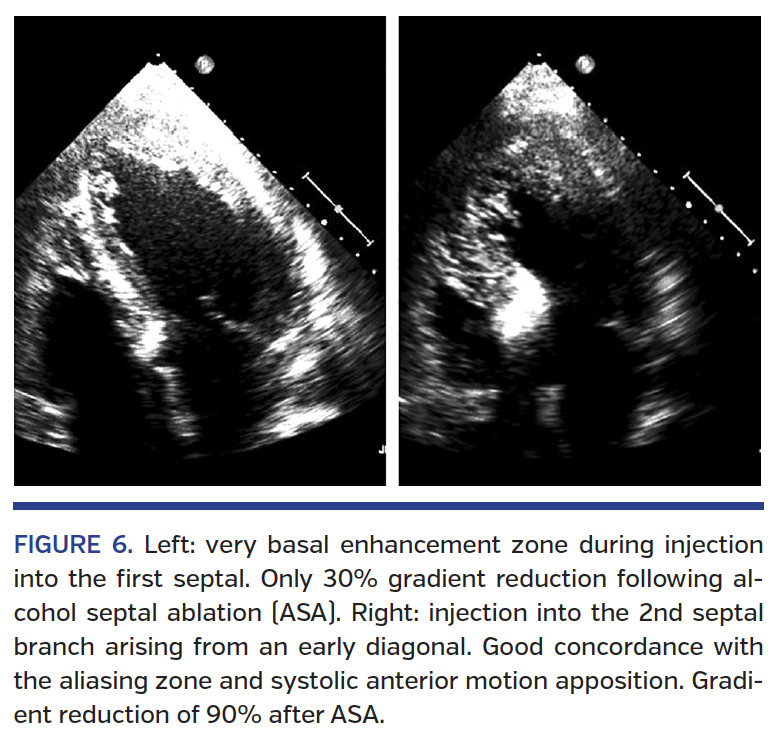

Following slow rinsing of the balloon lumen with 0.2-0.5 mL of saline, the balloon is deflated and the last criterion of ASA success can be verified: the presence of “no-reflow” in the treated septal branch. If the gradient is reduced by <50% and the echo-bright zone is inadequate, the contrast enhancement zone of a second septal branch can be assessed in order to treat this branch during the same procedure (Figure 6). Table 3 summarizes the key elements of a successful procedure.

numerous septal connections; and (3) confirm by concomitant echocardiography that the selected septal branch supplies the septal area obstructing the LVOT (echo-bright enhancement of the target septal area opposite the aliasing and systolic anterior movement apposition zone) (Figure 5).